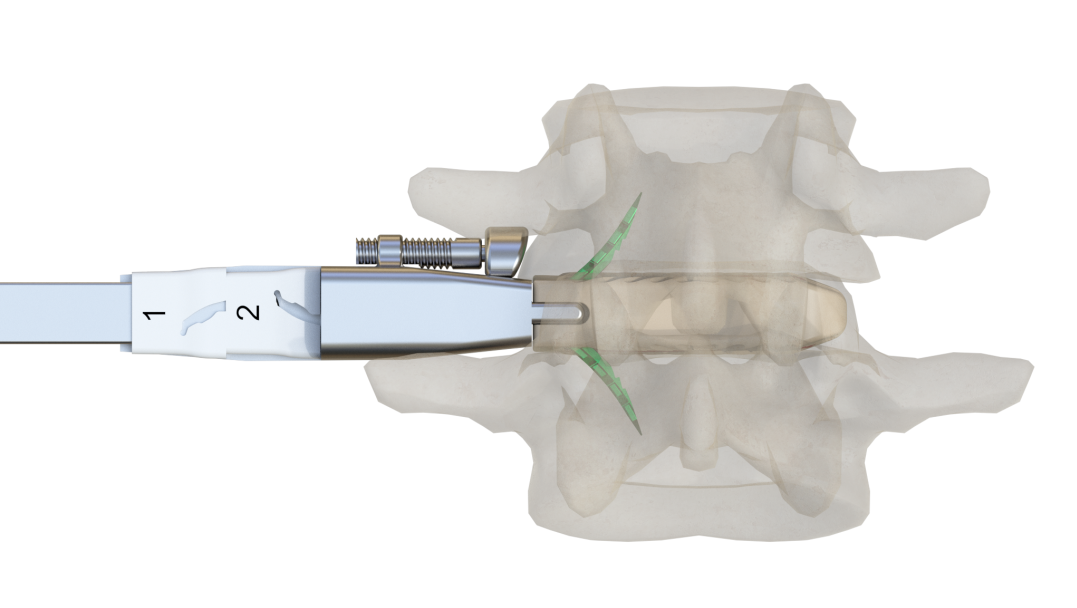

預(yù)彎的固定夾設(shè)計,交叉式自導(dǎo)向打入

根據(jù)不同椎體高度,選擇合適的固定夾

固定夾自限位設(shè)計,確保打入后穩(wěn)定性

固定夾可使責任椎間隙術(shù)后得到即刻穩(wěn)定,通過固定夾將融合器與上下終板錨定,增加了固定和負載界面,不但可防止融合器移位,還可分擔椎體終板應(yīng)力,減少融合器下沉的發(fā)生率。